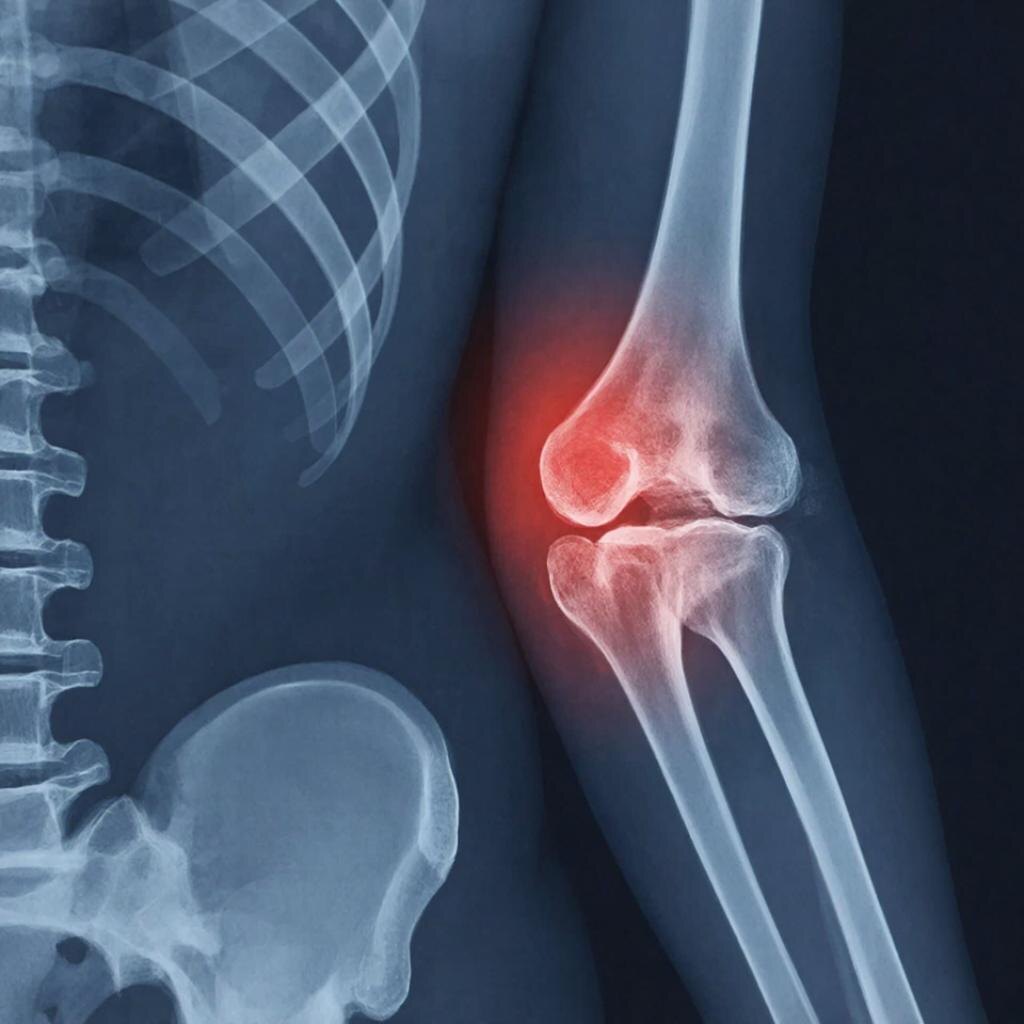

Елси у вас остеопороз задумайтесь о смене завтрака

Остеопороз: продолжаем кулинарный ликбез. Еще 5 завтраков для здоровья костей

В прошлый раз мы разобрали несколько вариантов утреннего меню, и судя по откликам, тема оказалась востребованной. Пациенты часто спрашивают: «Неужели придется питаться только творогом и рыбой?». Отвечаю: нет. Рацион может и должен быть разнообразным.

Главные принципы сохраняются: минимум соли (не более чайной ложки в сутки на всю еду), достаточно белка, присутствие кальция и его «помощников» — магния, витамина D и витамина К2. Представляю вашему вниманию еще пять идей для завтрака, которые легко впишутся в повседневную жизнь.